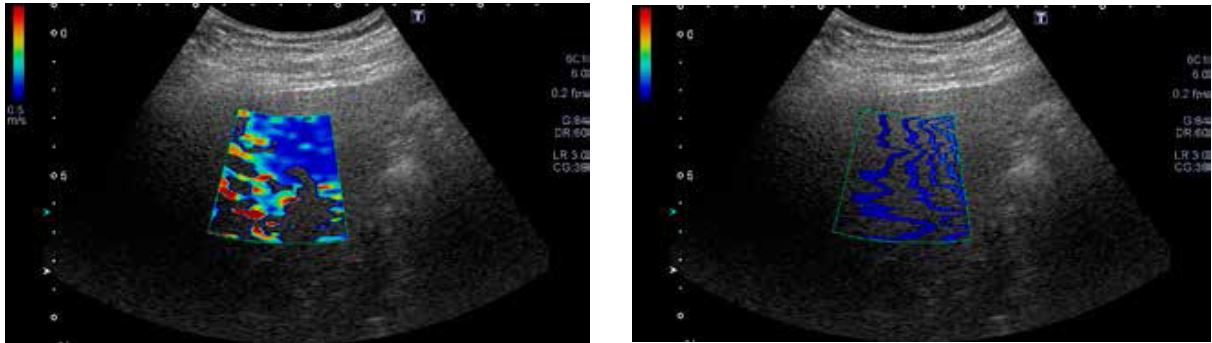

Нижче наведено випадок F1/A1 (хронічний гепатит) і випадок F4 (цироз) зі швидкістю зсувної хвилі 1,51 м/с і 3,32 м/с відповідно (рис. 10).

На основі кольорової карти колір змінюється з синього на жовтий/червоний, коли швидкість зсувної хвилі збільшується. Лінії на карті розповсюдження широко розділені в F4. Обидва випадки демонструють рівномірне поширення зсувних хвиль. Великі структури, такі як кровоносні судини на карту не потрапляють.

Середнє значення: 1,51 м/с. F1, A1 (хронічний гепатит)

Середнє значення: 3,32 м/с. F4 (цироз)

Рисунок 10. (а) Випадок хронічного гепатиту та випадок (б) цирозу печінки